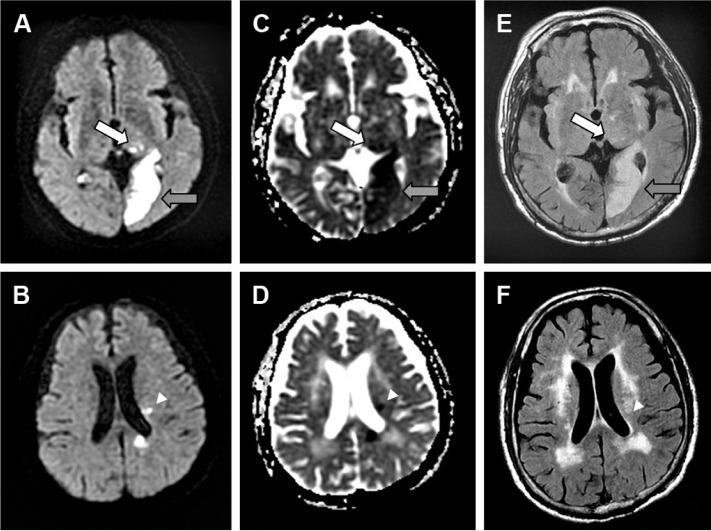

We present a 70-year-old man with left posterior cerebral artery infarction with quetiapine-induced punding manifesting as repetitive unidirectional body turning. Remission of punding behavior ensued after cessation of quetiapine and administration of clonazepam.